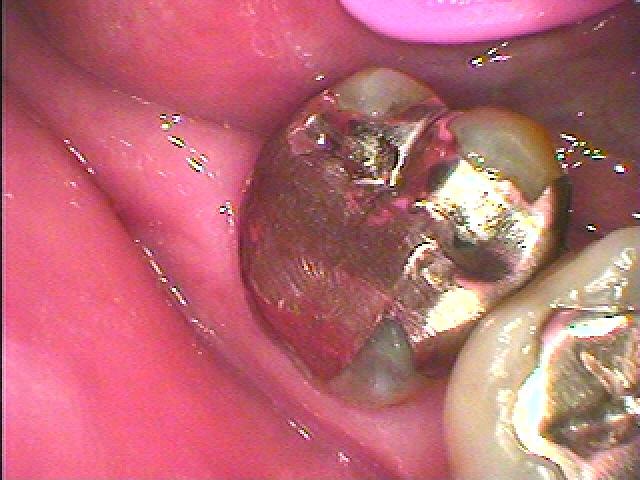

問題の歯になります

かなり大きな銀歯になります